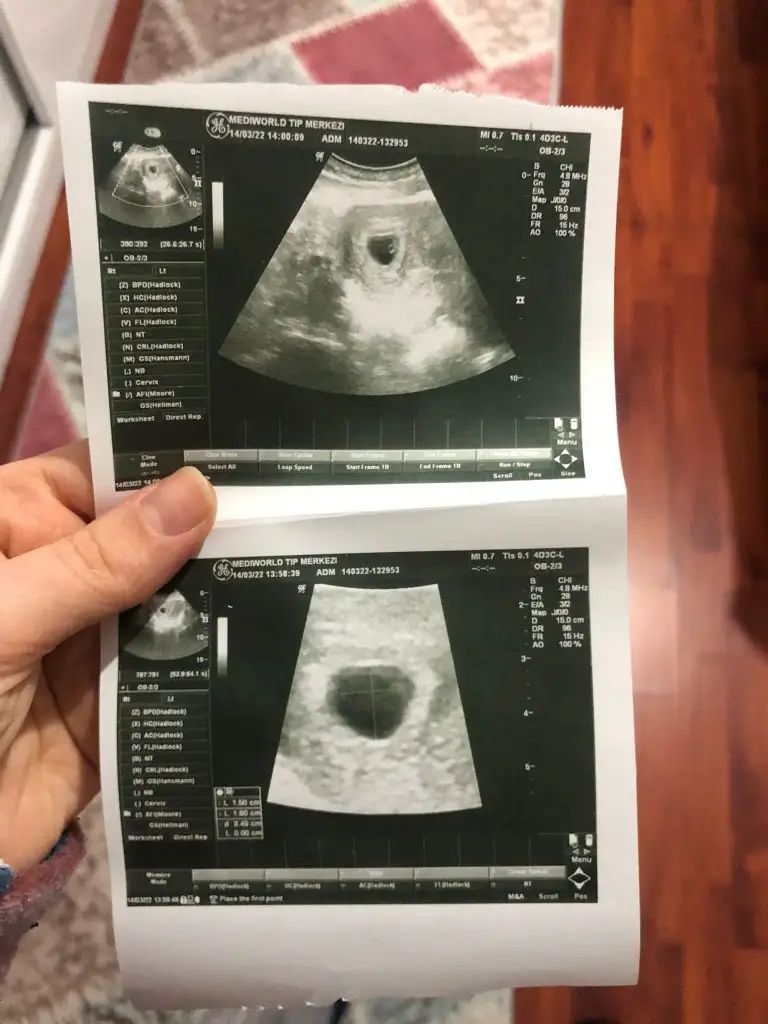

Bida bi arkadasimin bunuda yorumlayabilir misin ? Karindan.

Merhaba bende 9+6 haftalik hamileyim , karından bakildi, cinsiyeti sizce nedir? Her seyden once saglikli olsun ins, ilk bebegim olacakSelam Kızlarbir çok kişi gruplardan beni bilir. Yine yetiştim imdatlara

Tesekkur ederim cevabiniz icin, ogrenince net olarak size yazarimkuzucum günaydınAllah sağlıcakla kucağına aldırsın öncelikle Erkek gibi duruyor